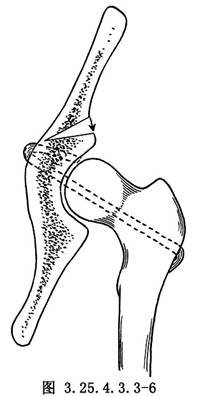

用4mm直徑斯氏針於大粗隆下緣向股骨頭中央鑽洞,將大粗隆基底帶蒂的髂脛束條縫成管狀,用有孔探針由大粗隆基底的骨洞穿入,由股骨頭中心拉出。再於髖臼中央偏前方,用骨鑽鑽洞,由髂骨內面的骨洞放入探針,將再造的圓韌帶由洞內拉出,將股骨頭復位,將圓韌帶拉緊與髖臼上緣的骨質和肌附麗再縫合固定,或於髂前下棘處鑽洞成襻狀縫合固定(圖3.25.4.3.3-3~3.25.4.3.3-6)。